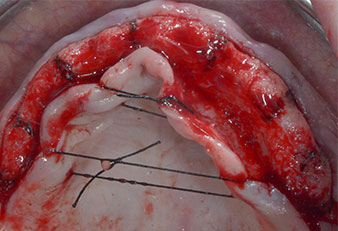

Fig. 2: Después de la incisión en la zona crestal media y de la preparación de colgajos mucoperiósticos, las posiciones del implante se transfirieron al hueso.

Debido al hueso relativamente duro (D2) existente en el sector anterior, los sitios de los implantes largos de 10 mm de las posiciones 11 y 21 se finalizaron con una fresa rotatoria de 4 mm de diámetro, en combinación con un contra-ángulo quirúrgico WS-75 L de W&H, el motor de implantes Implantmed de W&H y el módulo opcional Osstell ISQ de W&H. En cambio, debido a la existencia de hueso blando, los sitios posteriores se prepararon hasta un diámetro final de 3 mm utilizando el inserto Piezomed I3P. Por último, los implantes se colocaron a nivel crestal para su osteointegración durante tres meses (figuras 6-10). La prótesis existente se mantuvo sobre cuatro implantes provisionales (figura 8).

Implante en el nivel de tejido de 10 mm

Fig. 6: En la posición 21 se colocó un implante en el nivel de tejido de 10 mm. El implante de la posición 11 y los tres implantes posteriores izquierdos de 4 mm ya estaban colocados en su lugar.